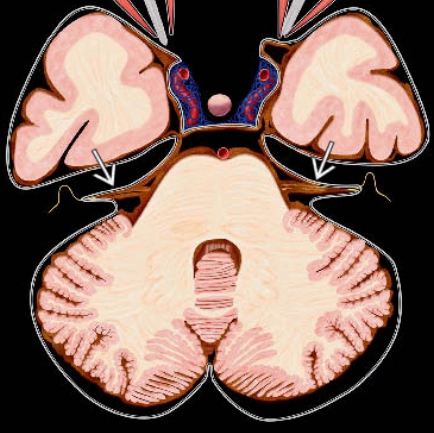

• Xuất huyết dưới nhện lồi não- cSAH (Convexal Subarachnoid Hemorrhage)